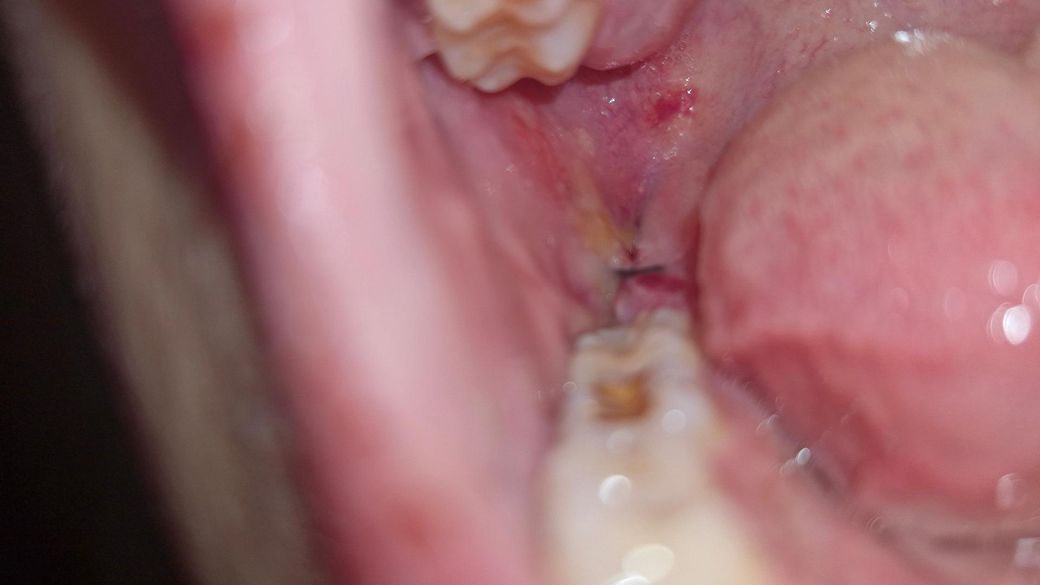

사랑니 발치 후 3일차인데 하얗고 노란? 물질이 생겼습니다

현재 사랑니 발치 후 3일차입니다. 아프진 않고 많이 부은 상태입니다. 반매복 사랑니를 뽑았던 자리에 하얗고 노란 이물질이 생겼는데 감염되버린 걸까요?

사진은 첫번째가 발치 1일차, 두번째가 현재입니다

• 2번 째 사진

사진상으로는 문제없이 잘 낫고 있는 것으로 보이며 하얀막은 정상적인 회복과정에서도 생깁니다.

사진에 보이는건 발치를 하고나서 잇몸이 아물면서 생기는 자연스러운 현상입니다. 크게 걱정하지 않으셔도 될것같습니다.

사진으로 봤을 경우에는 크게 문제가 있어 보이진 않습니다. 발칠한 부위에는 구멍이 있기 때문에 이물질이 들어갈 수 있습니다. 가볍게 가글을 하면 제거가 되며 대부분 시간이 지나면서 아물게 됩니다. 걱정이 되거나 해당 부위가 불편하다면 치과에서 진료를 받아보세요.